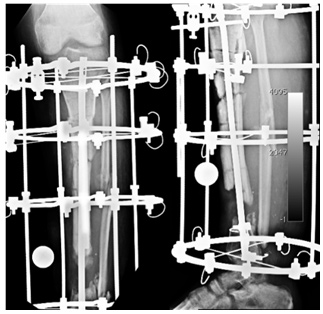

Bone Transport

The Ilizarov fixator is applied while the intra-medullary nail is still inside. An osteotomy was done in the proximal aspect for the purpose of bone transport.

5 Weeks